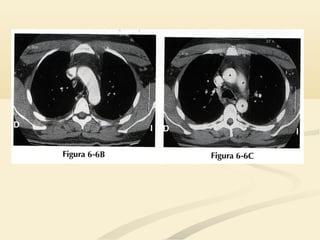

 Borde cardíacosuperior derecho y la aorta ascendenteBorde cardíaco superior derecho y la aorta ascendente son estructuras anteriores en el lado derecho.son estructuras anteriores en el lado derecho.  La aorta descendente es posterior en el lado izquierdo.La aorta descendente es posterior en el lado izquierdo.  La tráquea y el botón aórtico están localizadas en elLa tráquea y el botón aórtico están localizadas en el tórax mediotórax medio

• 18.

 El LSDocupa el tórax anterior y medio por encima deEl LSD ocupa el tórax anterior y medio por encima de la cisura menor.la cisura menor.  La consolidación del LSD causará un signo de la siluetaLa consolidación del LSD causará un signo de la silueta en el borde cardíaco derecho superior y en la interfaseen el borde cardíaco derecho superior y en la interfase traqueopulmonar derecha.traqueopulmonar derecha.

• 20.

 La consolidacióndel LSI borrará la aurícula izquierda,La consolidación del LSI borrará la aurícula izquierda, el botón aórtico y el mediastino anterior y medioel botón aórtico y el mediastino anterior y medio..